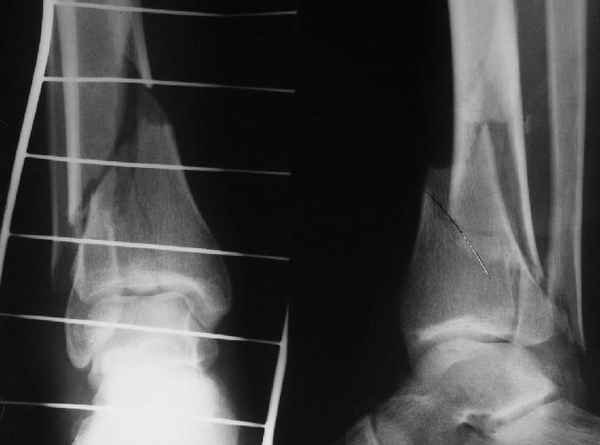

АЧ>Степень относительности этой стабильности все-таки довольно сильно может варьировать. Locked plate в сравнении с эластичным интрамедуллярным фиксатором - две большие разницы

Да и нет! Зависит от перелома и способа остеосинтеза. А результат? (01)

Мы же говорили о проксимальном плече. При переломе tibia, конечно, речи о двух Y-спицах нет. Еще раз о них - пружинящая подвижность без "срезающих" перемещений фрагментов - дополнительный стимул к образованию периостальной мозоли.

А в данном случае - у нас был бы применен locked nail с еще меньшими дырочками на коже и с возможностью полной нагрузки немедленно после операции. Какие тут аргументы в пользу выбора пластины, а не интрамедуллярного гвоздя?

АЧ>Какие тут аргументы в пользу выбора пластины, а не интрамедуллярного гвоздя?

Классически показанием для locked nail яв-ся зоны BC CD, до появления LCP показания к locked nail несколько расширялись в зоны AB и DE

Аргументы: перелом достаточно низкий, трудно будет ввести 3-и блок. винта, а учитывая характер перелома на 2-х дистальных винтах я бы не рекомендовал немедленную полную нагрузку.